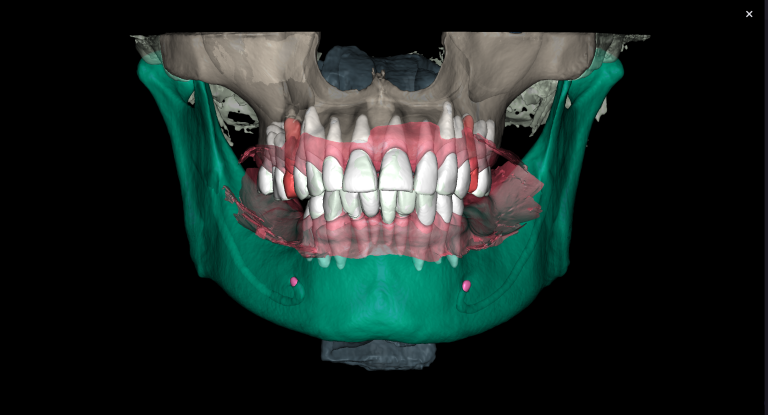

Diagnocat radiological report features an “Conditions with low probability” function. In this mode, teeth marked as “Low probability” are highlighted in yellow. Conditions such as caries and periapical lesions with a probability ranging from 30% to 50%

For example, in the area of tooth 22 (Universal 10), there is a label indicating “signs of caries.” However, they are poorly visualized at the CBCT

Additionally, thanks to the “Conditions with low probability,” signs of caries have been detected on the distal surface of tooth 24 (Universal 12)

If the probability percentage is over 50%, the teeth are highlighted in red, and the report contains information about the localization and depth of the lesions